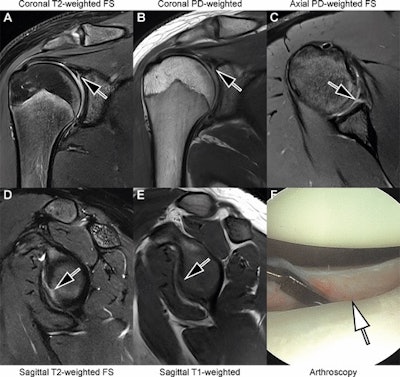

Images in an 18-year-old man with recurrent dislocations of the right shoulder. (A, B) Unenhanced coronal, (C) axial, and (D, E) sagittal deep learning super-resolution threefold parallel imaging -- accelerated turbo spin-echo MRI scans were obtained at 3-tesla field strength. (A) Coronal T2-weighted fat-suppressed (FS) and (B) coronal proton density (PD)-weighted MRI scans show a nondisplaced superior labral tear (arrows). (C) Axial proton density-weighted fat-suppressed, (D) sagittal T2-weighted fat-suppressed, and (E) sagittal T1-weighted MRI scans show continuation into a nondisplaced anteroinferior labral tear (arrows). All seven readers correctly diagnosed the arthroscopy-validated findings. (F) An arthroscopic photograph shows the anteroinferior labral tear (arrow). Image and caption courtesy of the RSNA.

Images in an 18-year-old man with recurrent dislocations of the right shoulder. (A, B) Unenhanced coronal, (C) axial, and (D, E) sagittal deep learning super-resolution threefold parallel imaging -- accelerated turbo spin-echo MRI scans were obtained at 3-tesla field strength. (A) Coronal T2-weighted fat-suppressed (FS) and (B) coronal proton density (PD)-weighted MRI scans show a nondisplaced superior labral tear (arrows). (C) Axial proton density-weighted fat-suppressed, (D) sagittal T2-weighted fat-suppressed, and (E) sagittal T1-weighted MRI scans show continuation into a nondisplaced anteroinferior labral tear (arrows). All seven readers correctly diagnosed the arthroscopy-validated findings. (F) An arthroscopic photograph shows the anteroinferior labral tear (arrow). Image and caption courtesy of the RSNA.

For instance, the scans allowed the readers to correctly categorize the supraspinatus-infraspinatus tendons as normal versus partial-thickness tear versus full-thickness tear with a sensitivity of 89%, a specificity of 90%, and an accuracy of 89%. They also achieved a sensitivity of 93%, a specificity of 73%, and an accuracy of 86% for diagnosing tears of the superior labrum.